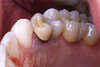

IMPLANTATION

Extraction, Implantation